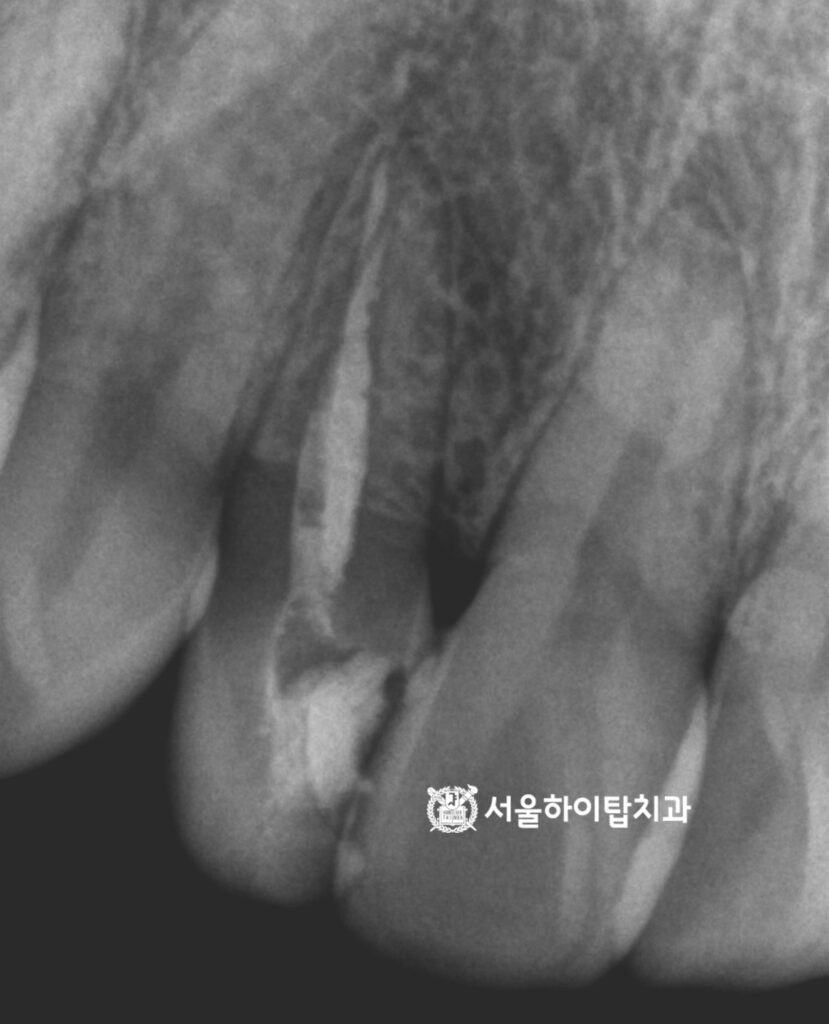

그다음, 마스터 콘을 기준으로 하여

가타퍼차를 가압하는 방식(가압근충)으로

근관 전체를 채워 밀폐합니다.

이 과정은 재료를 압축해

내부에 빈 공간이 생기지 않도록 막아

감염을 방지하는 중요한 단계입니다.

근관이 완전히 밀폐되면,

치관 부분에 남아 있는 빈 공간을

단단하게 채우는 코어(Core) 수복을

진행하게 됩니다.